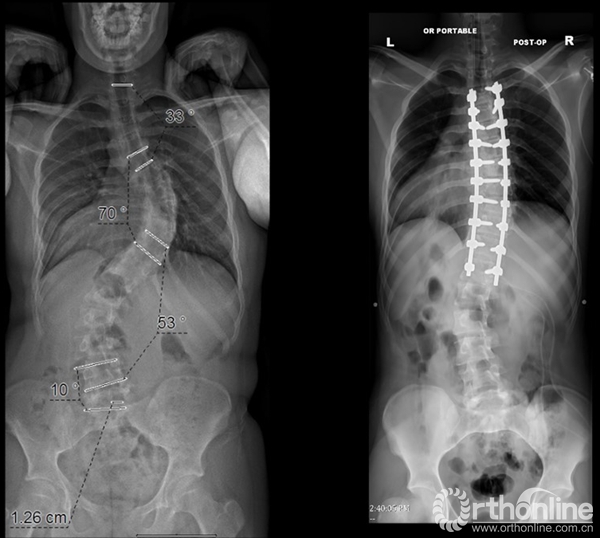

这个病例是林老师在2017年SRS年会上,展示了一个Lenke3型的病人。按照以往的Lenke分型,需要融合主胸弯和腰弯,但是林老师目前只进行胸弯的融合,保留了腰弯,术后患者的生活质量获得很大的提升。

这是林老师突破自己制定的治疗标准的尝试,这样的手术计划在未来的Lenke侧弯分型完善版中,将会进行详细的阐述。